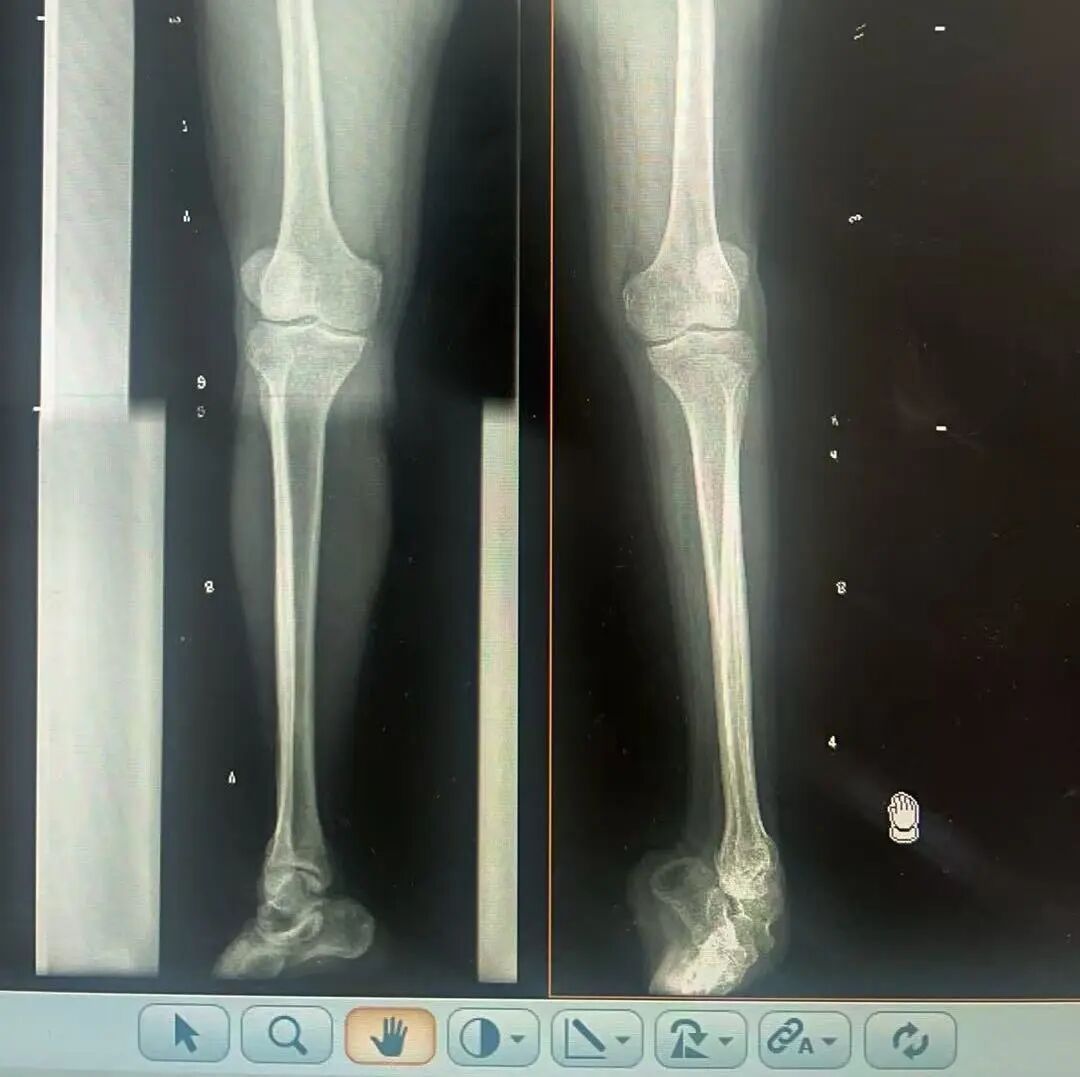

術(shù)前X光片 VS 術(shù)后治療效果

骨科隨即為陽(yáng)先生進(jìn)行了全面的檢查。診斷明確而復(fù)雜:陽(yáng)先生患有脊髓灰質(zhì)炎后遺癥、左踝馬蹄內(nèi)翻足、骨盆傾斜……面對(duì)這張沉甸甸的診斷書(shū),由肢體功能重建顯微修復(fù)學(xué)科組長(zhǎng)鄭群龍所帶領(lǐng)的醫(yī)療團(tuán)隊(duì)沒(méi)有畏懼,“這是一個(gè)家庭38年的堅(jiān)守與期盼,我們必須全力以赴”

針對(duì)陽(yáng)先生的復(fù)雜情況,鄭群龍醫(yī)師團(tuán)隊(duì)制定了詳盡的手術(shù)方案:左踝關(guān)節(jié)融合+馬蹄足畸形矯正+跟腱延長(zhǎng)+外固定架固定術(shù)。手術(shù)的核心,正是伊里扎洛夫技術(shù)。這項(xiàng)技術(shù)如同精密的“時(shí)空建筑學(xué)”,通過(guò)微創(chuàng)安裝環(huán)形外固定架,前足-后足安裝鋼環(huán),再將足的鋼環(huán)與脛骨的固定鋼環(huán)在踝關(guān)節(jié)前、后、左、右用帶關(guān)節(jié)的螺紋桿連接,由此構(gòu)建成一個(gè)能體外牽拉調(diào)控的三維立體構(gòu)型,在術(shù)后進(jìn)行精準(zhǔn)、緩慢的調(diào)整,一寸一寸逐步將畸形的骨骼、軟組織恢復(fù)到正常位置。

9月1日,在全麻狀態(tài)下,陽(yáng)先生接受了伊里扎洛夫外固定架安裝術(shù)。鄭群龍團(tuán)隊(duì)在陽(yáng)先生左足足踝部植入克氏針及半針,安裝外固定架,通過(guò)支架的機(jī)械結(jié)構(gòu)對(duì)馬蹄內(nèi)翻畸形進(jìn)行緩慢、持續(xù)的牽拉矯正。術(shù)后,鄭群龍團(tuán)隊(duì)反復(fù)指導(dǎo)訓(xùn)練陽(yáng)先生父子進(jìn)行外固定架的日常調(diào)試,按照預(yù)定計(jì)劃每日調(diào)整螺桿,逐漸糾正足部畸形,并配合專業(yè)的康復(fù)訓(xùn)練,包括踝關(guān)節(jié)主動(dòng)及被動(dòng)活動(dòng)、下肢肌力訓(xùn)練等項(xiàng)目促進(jìn)陽(yáng)先生腿部肢體功能恢復(fù),預(yù)防肌肉萎縮及關(guān)節(jié)僵硬。